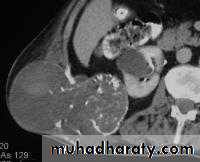

XRMetaphyseal lesion

Usually around the knee

Osteolytic & osteoblastic areas

Soft tissue invasion sun-ray appearancePeriosteal elevation Codman`s triangle

CT + surgery

5 yr survival : 60 %